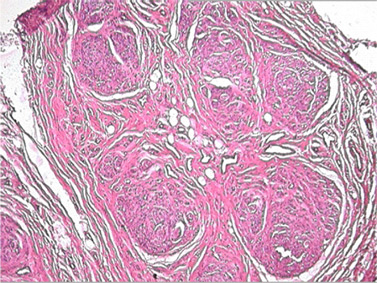

Fig. 2:  Histopathology showing infiltration of nerve fascicles by mature adipose cells.

X rays showed a soft tissue mass in forearm and hand without evidence of bony hypertrophy or calcification.MRI report hinted at possibility of hemangioma due to appearance of tortuous voids in soft tissue mass. Since the swelling was interfering with his work, it was decided to debulk the tumor. The swelling was found to be greyish tumor 16x7.5x5 cm [Fig. 1] in size extending to hand through carpal tunnel. It was an octopus like mass with multiple linear extensions in all directions, and was not capsulated. Finger like extensions were found to be attached to under surface of skin of hand. The tumor was adherent to surrounding structures including flexor tendons and lumbricals but was not attached to median nerve.  Sub-total excision of tumor was carried out without cutting transverse carpal ligament. A part of tumor extending to dorsal aspect of first introsseous space was not removed. Post-operatively, wound healed normally. However, he developed decreased sensations of index and middle fingers. Histopathology was reported as Lipomatous hamartoma [Fig. 2].